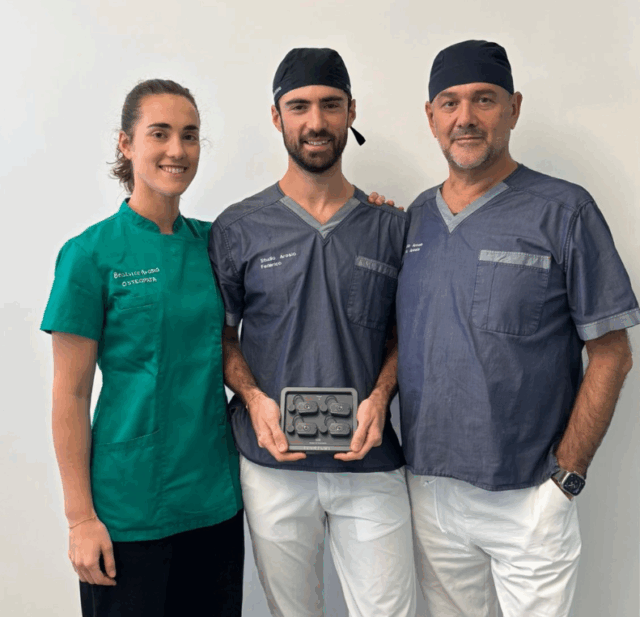

Molte terapie vengono proposte senza una valutazione approfondita e senza strumenti adeguati per una diagnosi realmente accurata. Lo Studio Dentistico Arosio, in sinergia con lo Studio Osteopatico Arosio, si distingue per un approccio integrato e tecnologicamente avanzato nella gestione di questi disturbi. Un supporto essenziale nella fase diagnostica è rappresentato da Teethan (figura 1 e 2), un dispositivo medico non invasivo che analizza l’attività dei muscoli masticatori e cervicali, rilevando eventuali sovraccarichi e squilibri. Questo consente di individuare con precisione problematiche legate all’occlusione e alla tensione muscolare, permettendo di definire il trattamento più adatto per ogni paziente.

Affrontare queste problematiche richiede spesso un intervento congiunto tra odontoiatra e osteopata. Grazie alla collaborazione tra i due studi, è possibile agire in modo mirato e risolutivo, integrando diverse soluzioni terapeutiche: manipolazioni osteopatiche per riequilibrare le tensioni muscolari e articolari (figura 3 e 4); esercizi personalizzati da svolgere a casa per migliorare la postura e ridurre lo stress muscolare; bite intraorali per proteggere la dentatura e ottimizzare l’occlusione (figura 5); riabilitazioni protesiche per correggere restauri non funzionali; trattamenti con tossina botulinica, in collaborazione con una specialista in medicina estetica, per rilassare la muscolatura e alleviare il dolore. Liberarsi da cefalee croniche, dolori mandibolari e fastidi cervicali è possibile, ma solo attraverso una diagnosi corretta e un percorso terapeutico multidisciplinare. Rivolgersi a centri specializzati come lo Studio Dentistico Arosio e lo Studio Osteopatico Arosio è la scelta giusta per ritrovare il benessere e risolvere in modo definitivo queste problematiche.

Per qualunque informazione lo Studio dentistico del dottor Paolo Arosio e Beatrice Arosio Osteopata vi aspettano nella sede di via Don Lualdi 4/C a Vimercate (tel. 039.6085229 – 3202676512)